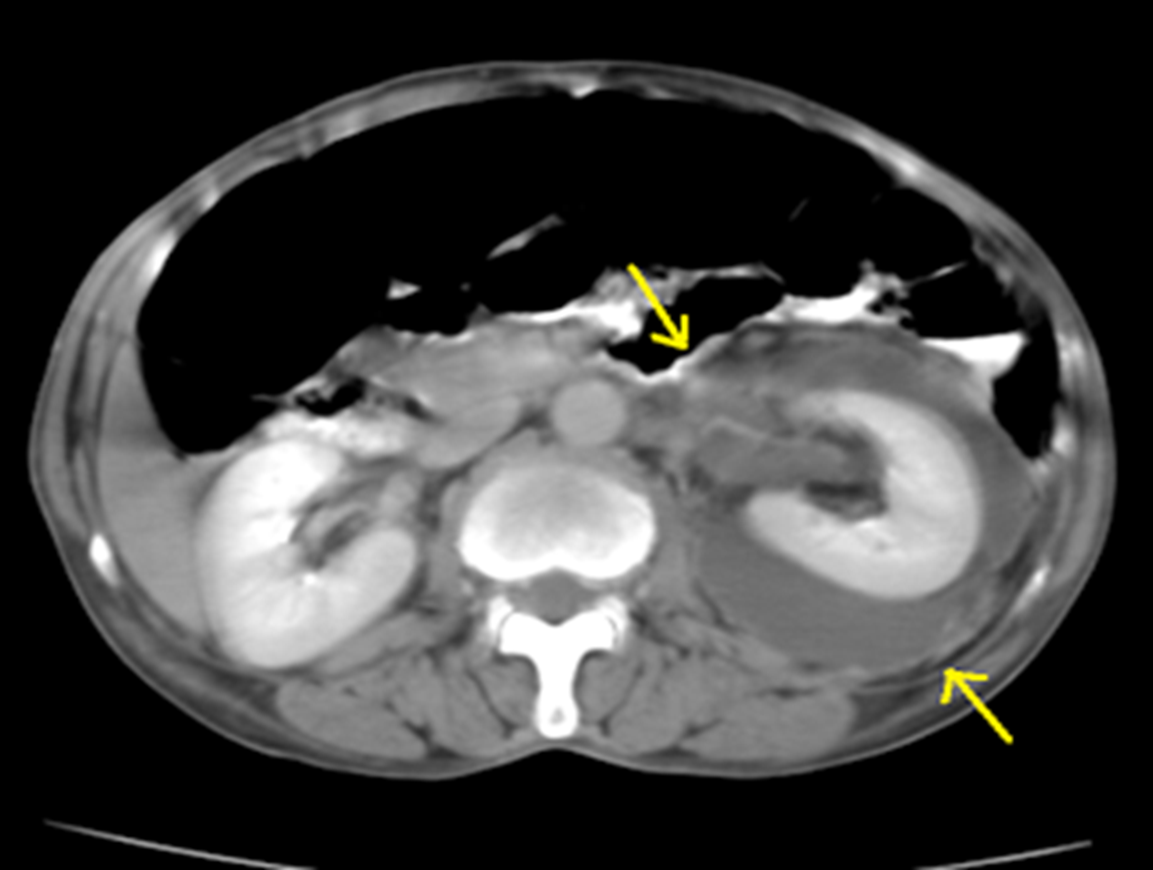

Perirenal collection Perinephric abscess.

CT scan showing loculated fluid (arrows) with a thick enhancing wall surrounding the left kidney.